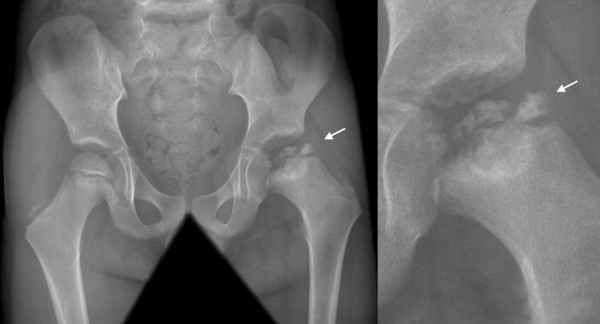

Tổn thương cơ bản của bệnh là hoại tử nhân của chỏm xương đùi. Phần đầu xương, lúc đầu là hoại tử, tiếp sau đó bị xâm lấn bởi phản ứng của mạch máu và tổ chức liên kết. Trong giai đoạn cuối, các tổ chức xương còn hoạt động sẽ thay thế phần hoại tử. Điểm cơ bản của bệnh chính là sự phục hồi xương tiến triển trong một khoảng thời gian dài (2 – 4 năm), chỏm xương đùi hết sức mềm, có xu hướng xẹp lại, do đó mà bệnh có tên là coxa plana. Các thành phần bao khớp – màng hoạt dịch phản ứng bằng cách tăng sản mạch máu – tổ chức liên kết, tăng sinh thâm nhiễm, sau đó là xơ. Giai đoạn tiếp theo, các thành phần xương và bao khớp – màng hoạt dịch dễ dàng bị thoái hóa thứ phát hoặc biến dạng khớp ở giai đoạn muộn hơn nữa. Tiến triển của bệnh tương đối nhanh nếu không được phát hiện. Thí dụ trên phim chụp của một bệnh nhân 13 tuổi, chỉ sau 3 tháng, không được điều trị, không được tư vấn, chỏm xương đùi trái đã bị hủy một cách rõ rệt.

Trong giai đoạn khởi phát, bệnh thường có hai dạng triệu chứng gián tiếp và trực tiếp. Trên phim X-quang của giai đoạn gián tiếp thường xuất hiện: khe khớp rộng ra (chỏm xương đùi dường như xa đáy ổ cối, nhất là ở phần dưới). Phần đầu xương thay đổi (có các điểm lốm đốm làm đầu xương không đồng đều, đôi khi có các khuyết nhỏ ở viền sụn liên hợp đầu xương, mất chất khoáng. Triệu chứng của giai đoạn trực tiếp là hình ảnh kết đặc nhân của chỏm xuơng đùi, biến đổi phần kết cấu của chỏm, hình ảnh “dấu ấn móng tay” (vùng sáng phân cách với ổ khớp bởi một mảnh xương). Bước sang giai đoạn hoại tử, các biến đổi nhân của chỏm trở nên rõ rệt: chỏm dẹt (có hình ảnh “mũ bêrê” hoặc “đệm ghế tàu hỏa”; kết cấu của chỏm không đều, thay đổi đầu xương kèm theo khe liên kết giữa đầu xương và chỏm rộng ra, tạo nên hình ảnh”đầu quả chùy”của cổ xương đùi. Thời gian tiến triển trung bình diễn ra trong khoảng 2 – 3 năm.